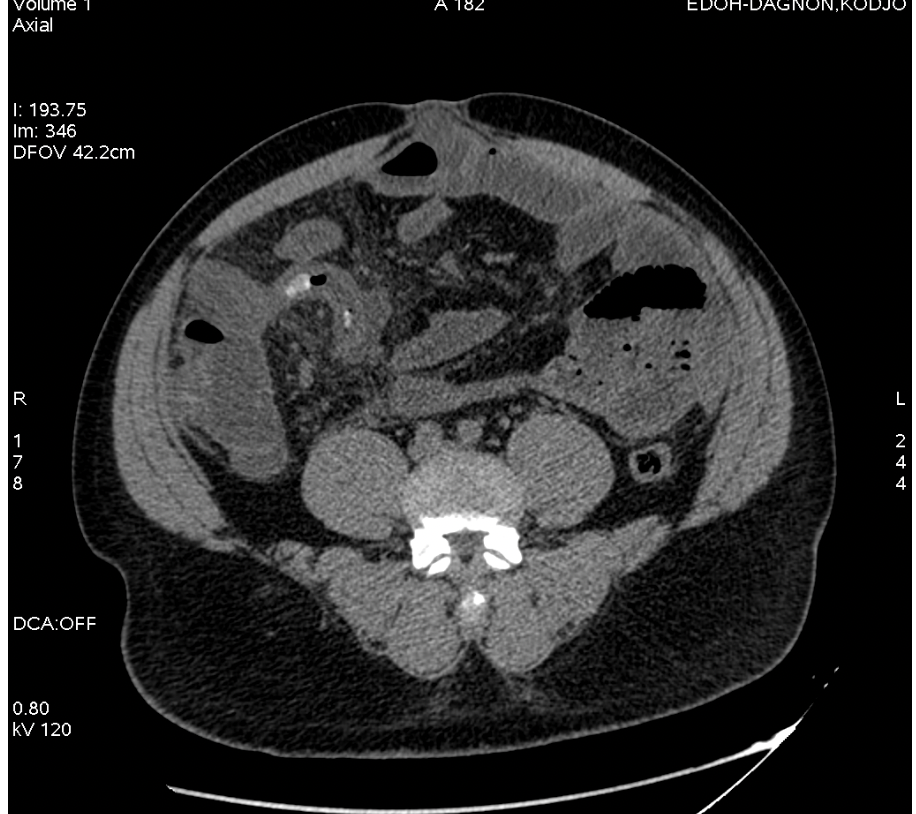

Aspect TDM appendicite dite typique

A

• Augmentation taille appendice et paroi

• Infiltration graisse du méso appendice

• Présence éventuelle stercolithe

• Présence éventuelle complication